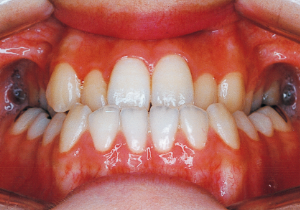

2 After Phase 2 Treatment 5-9-’92

This case presented with Class III malocclusion and significant negative overjet from the early mixed dentition. Regular observation was conducted, and Phase I treatment was initiated after the eruption of the anterior teeth, improving the anterior occlusal relationship and molar relationship. Subsequently, regular observation continued toward the completion of the permanent dentition. However, due to vigorous mandibular growth, orthodontic treatment including surgery became necessary.

Aware that treatment would be challenging, we proceeded with the first phase of treatment based on the current functional status and anticipated developmental implications (7). During the mixed dentition phase, the body responds readily to treatment, allowing for relatively rapid tooth movement and changes in jaw position (8,9). Subsequently, once freed from mechanical stimulation, growth continues according to inherent predispositions, often appearing to disregard occlusal functional efficiency (10,11). These changes are clearly observable on cephalometric radiographs (12). After confirming the extent and direction of growth, we decided to incorporate surgical intervention into the treatment plan and wait until the age when growth begin to decline.